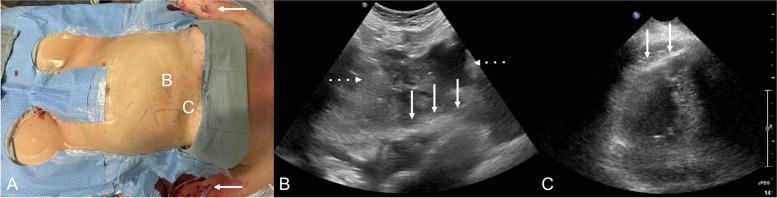

Materials and methods: An institutional protocol was established for intraprocedural transthoracic echocardiographic monitoring during the TCVO recanalization procedures. The lower chest and upper abdomen were prepared within the sterile field. A separate stand was set up with unopened supplies needed for pericardial drain placement. Intermittent echocardiographic monitoring was performed throughout the TCVO procedure using a dedicated curvilinear probe prepared on the field. If indicated, an image guided pericardial drain was placed expeditiously.

Results: Four cases of cardiac tamponade were encountered during or immediately post-procedure. All cases demonstrated technically successful and prompt pericardial drain placement with immediate reversal of the tamponade physiology.